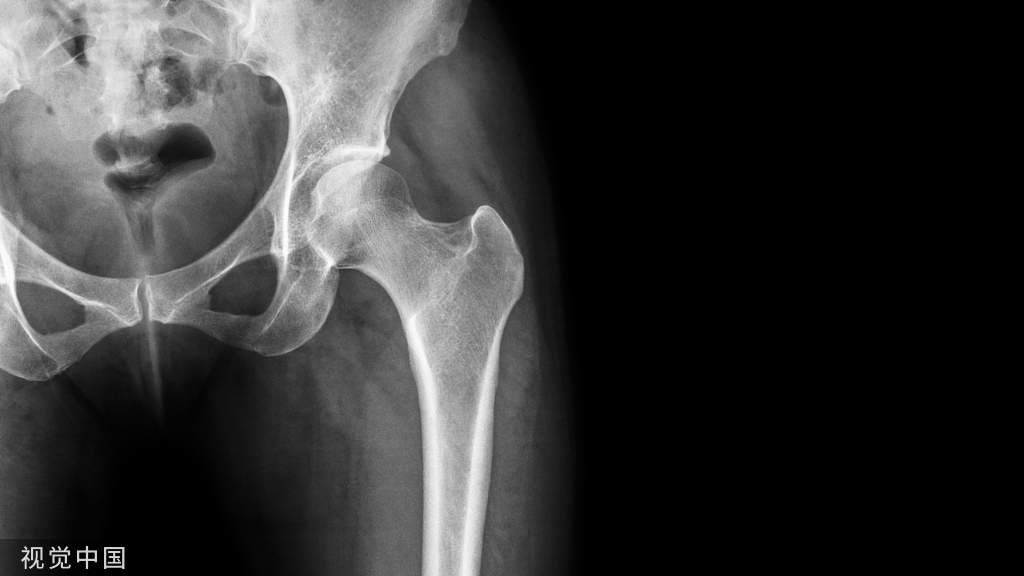

(1)X线平片常规正、侧、轴位X线平片少有异常发现,但可以排除肘关节的合并疾病,如骨关节炎时关节后外侧旋转不稳定等。偶尔会发现钙化性腱鞘炎。